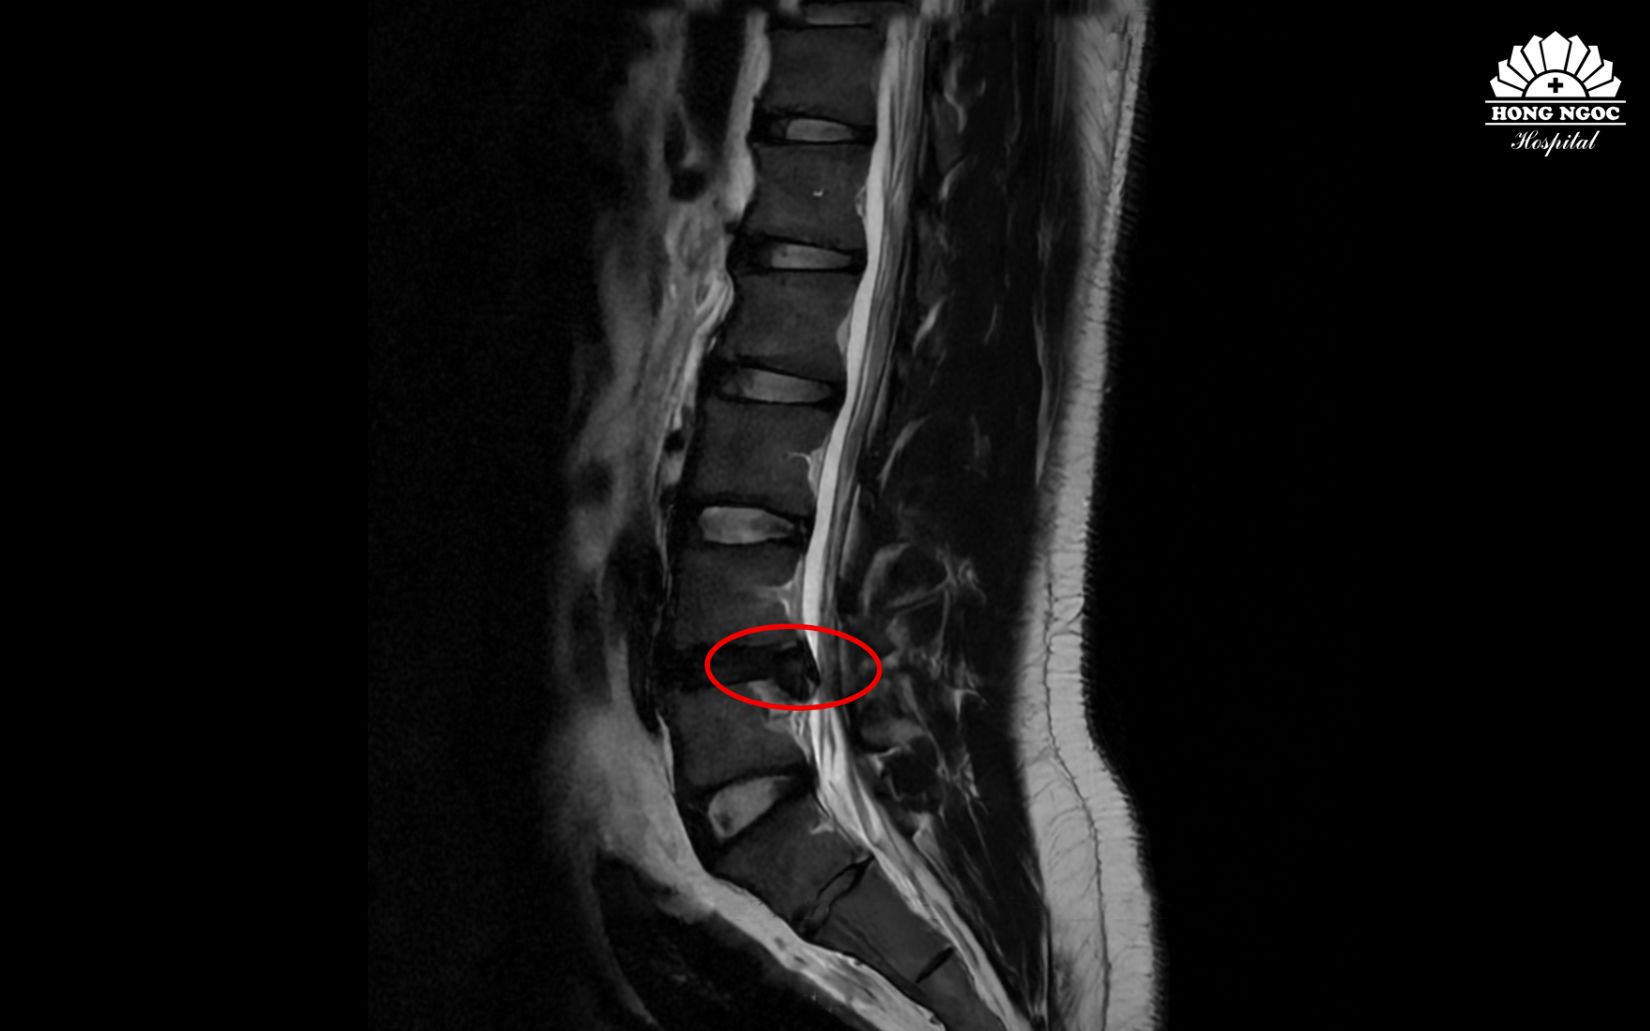

Qua thăm khám và kết quả chụp cộng hưởng từ (MRI), bệnh nhân được chẩn đoán thoát vị đĩa đệm cột sống thắt lưng L4/L5 gây chèn ép rễ thần kinh, cần phẫu thuật để tránh biến chứng liệt.

Hình ảnh thoát vị đĩa đệm cột sống L4/L5 qua phim chụp

Trực tiếp thăm khám cho bệnh nhân, PGS.TS.BS Hà Kim Trung (Phó Giám đốc Y khoa BVĐK Hồng Ngọc - Phúc Trường Minh) phân tích: Thoát vị đĩa đệm thắt lưng ngày càng phổ biến ở người trẻ, nhất là những người ngồi lâu, ít vận động như nhân viên văn phòng hay lái xe,.. Bệnh nhân này mới 28 tuổi đã gặp tình trạng thoái hóa gây tổn thương lớp sụn thân đốt sống, thoát vị chèn ép rễ thần kinh gây đau cấp tính và có mất vững cột sống. Vì vậy, phẫu thuật sớm không chỉ giúp giải phóng chèn ép, làm vững cột sống mà còn rút ngắn thời gian hồi phục, hạn chế biến chứng thần kinh và sớm trở lại lao động, chơi thể thao bình thường.